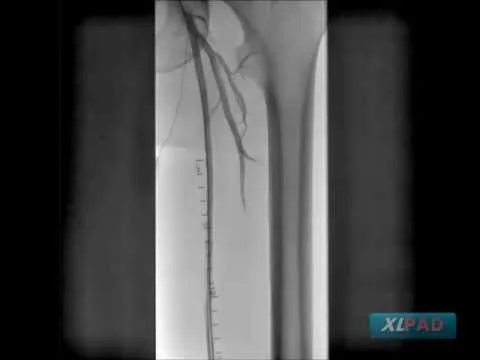

Viance to Cross CTO with Atherectomy